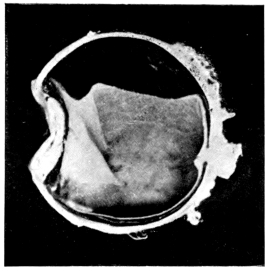

PLATE IV.

22.

LENS DISLOCATED BEHIND RETINA

curly bracket span

48

23.

FISTULA OF THE CORNEA

24.

CAPSULO-CORNEAL SYNECHIA

25.

RETINO-CORNEAL SYNECHIA

26.

SCLERAL FISTULA

27.

"    " (MAGNIFIED)